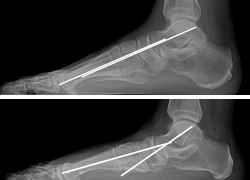

(Top) An x-ray of a normal foot. Note that the lines are parallel, indicating a normal arch. (Bottom) In this x-ray the lines diverge, which is consistent with flatfoot deformity.